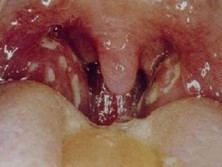

阿斯匹林不耐受三联症

(又名Wiolal综合征)

阿斯匹林不耐三联症或称为阿斯匹林不耐三联症Wiolal综合征是一种原因不明的呼吸...